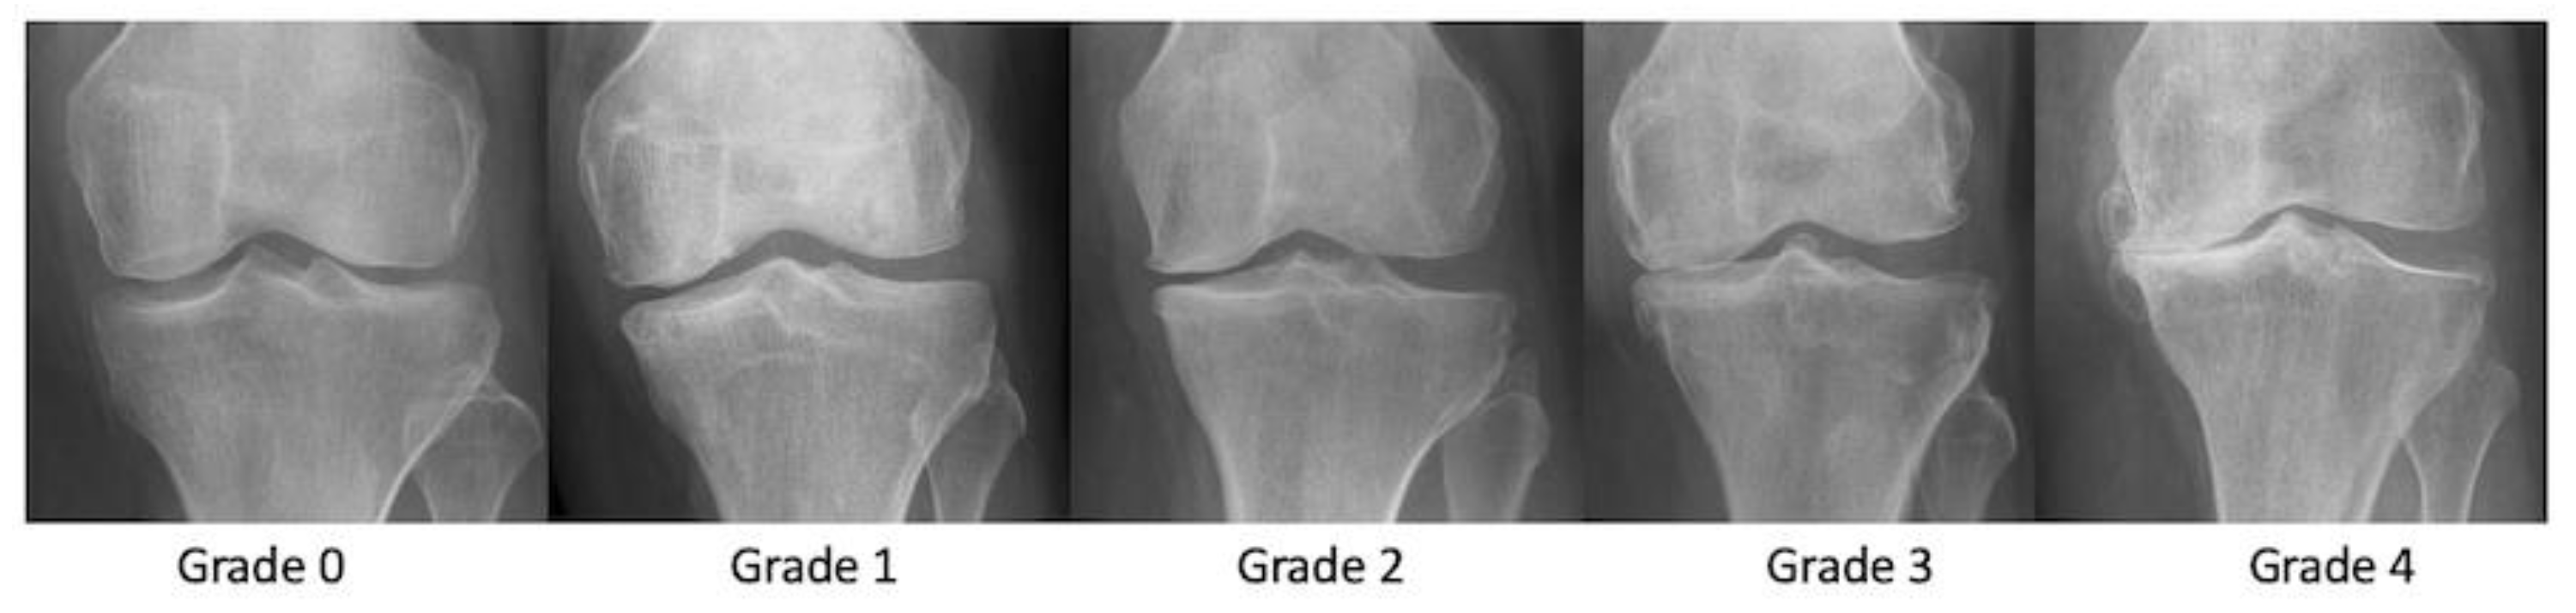

3.1. Radiographs